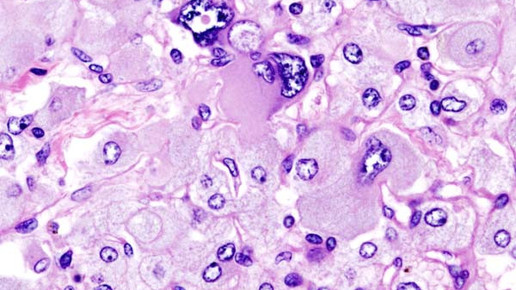

Die Tumorarten Phäochromozytom und Paragangliom sind dafür bekannt, dass sie in hohem Maß Catecholamine sezernieren – Substanzen, die das zentrale Nervensystem stimulieren. Die neuroendokrinen Tumore treten vor allem bei Erwachsenen zwischen dem 40. und 50. Lebensjahr auf – doch immerhin 10 Prozent der Betroffenen sind Kinder, die meist eine genetische Disposition besitzen.

Patienten, bei denen die Tumoren auftreten, klagen häufig über Bluthochdruck. In der Folge treten Herzrasen, Kopfschmerzen oder Schwindel auf. Die Erkrankung geht einher mit einer bösartigen Vergrößerung der Nebenniere, welche unbehandelt tödlich verlaufen kann.